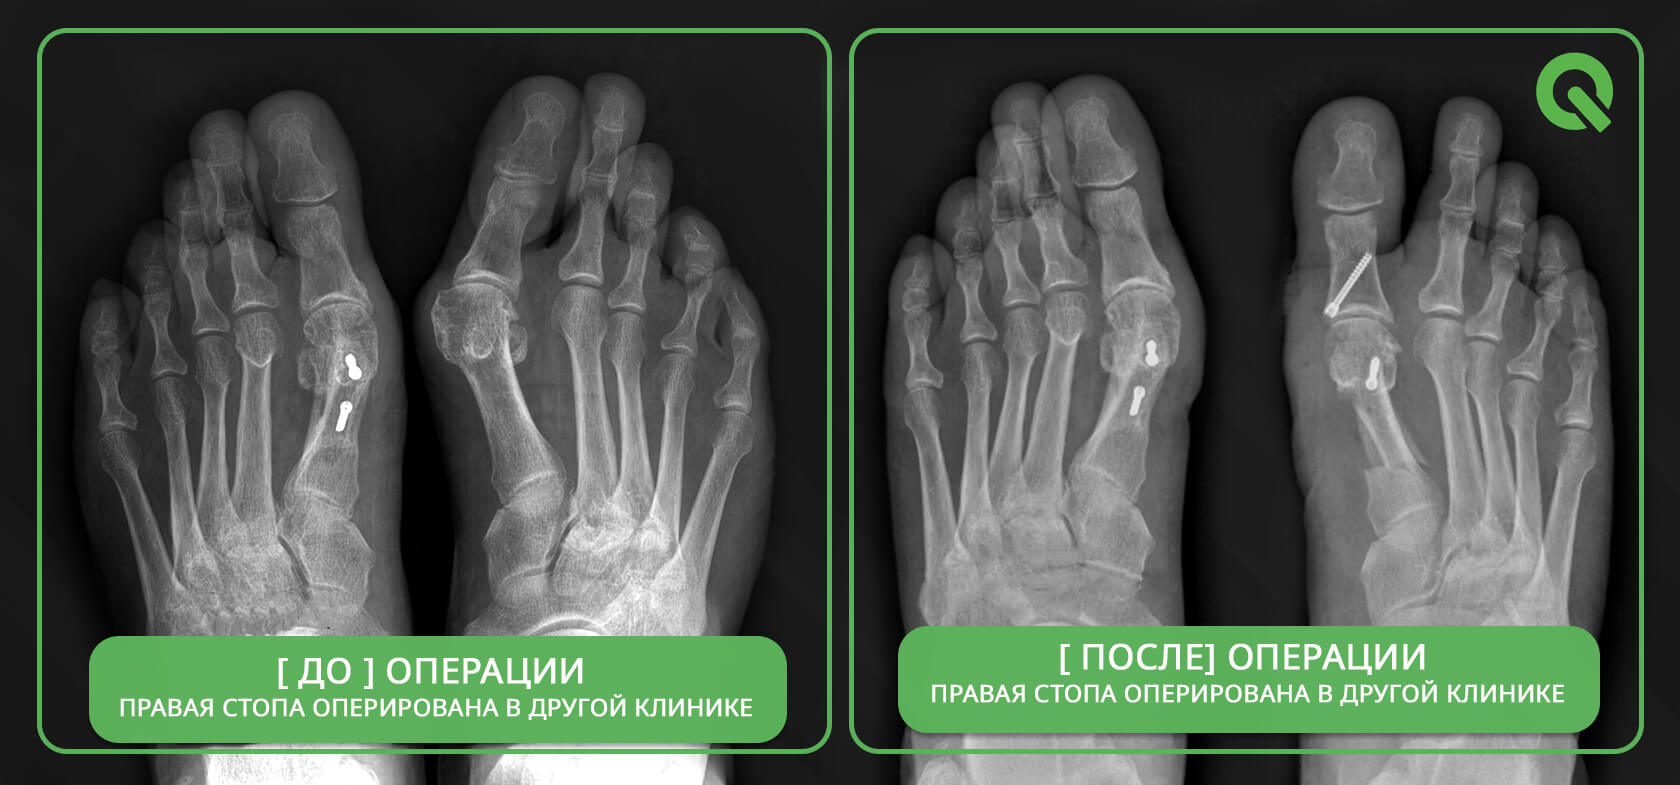

Операция Вальгусная Деформация Фото

Операция Вальгусная Деформация Фото 113 фотографий